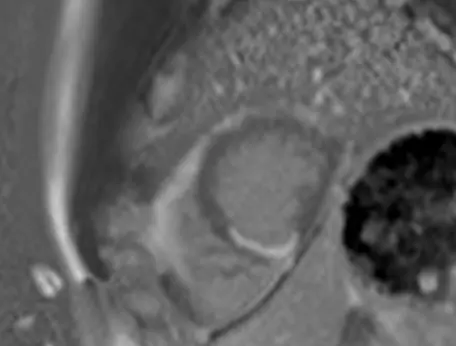

Subendocardial infarct

LGE visualized on PSIR (SAX view with motion correction) reported as “Moderate size area of subendocardial late gadolinium enhancement in the inferior wall consistent with prior presumptive diagnosis of SCAD in the PDA.”